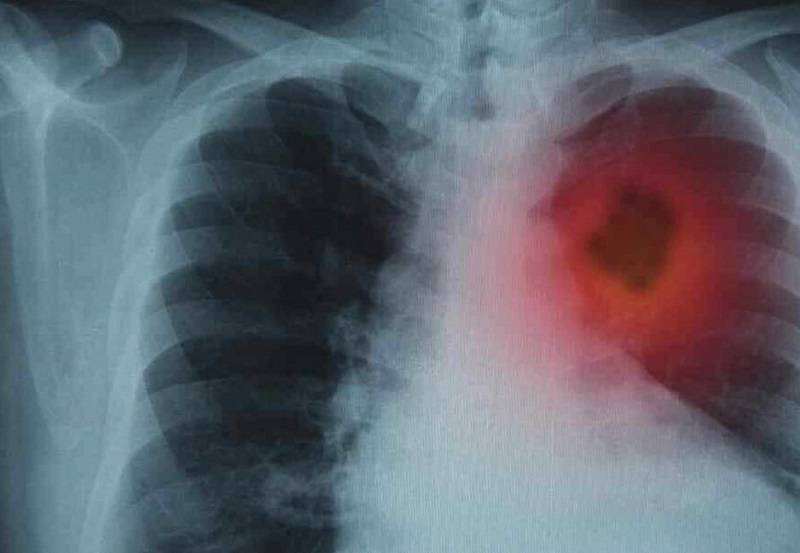

Yaklaşık 30 yıl sigara kullandıktan sonra sağlıklı hayat merkezine başvuran 49 yaşındaki Ali Duran, sigarayı bırakma sürecine ilişkin yaşadıklarını anlattı. Kalp rahatsızlığı nedeniyle doktorunun tavsiyesi üzerine sigarayı bırakmaya karar verdiğini belirten Duran, sigara bırakma polikliniğinde görev yapan hekimler ve uzman ekipler tarafından detaylı şekilde bilgilendirildiğini, gerekli ölçümlerin yapıldığını ve psikolojik destek aldığını ifade etti. Yaklaşık 3 aydır sigara kullanmadığını ifade eden Duran, nefes alışverişinin düzeldiğini, merdivenleri rahatlıkla çıkabildiğini ve enerjisinin arttığını belirterek, sigarayı bırakmak isteyen vatandaşları sağlıklı hayat merkezlerine davet etti.

Sigara bırakmak isteyen hastalarla sürecin karbonmonoksit ve tansiyon ölçümleriyle başladığını ifade eden Dr. Berçin, hastalarla birlikte belirlenen sigara bırakma planı doğrultusunda ilk haftanın ardından yüz yüze görüşmeler yaptıklarını, devam eden süreçte ise aylık takiplerle gerek telefonla gerek yüz yüze görüşmeler gerçekleştirdiklerini aktardı.